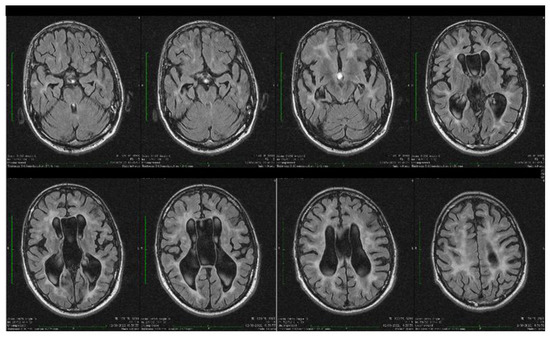

| Stoian et al. (our own case) | Case report | Male/4.5 months | Tonic seizures; later in evolution a left facial hemi spasm | 31 years | Reduced visual acuity (myopia), one and a half syndrome with left abduction nystagmus, left facial hemi spasms, divergent strabismus, flaccid tetra paresis, bilateral inconstant Babinski sign, gait instability, truncal ataxia, | Mild facial dysmorphism with thin upper lip and slightly spaced teeth | Social isolation, bradypsychia, bradylalia, echolalia, minimal linguistic baggage, behavioral stereotypes, MMSE17 points | Cryptorchidism | EEG: Poor unmodulated alpha activity, frontal intermittent theta activity; sharp waves and sharp peaks on the left central, parietal and temporal derivations | Brain CT: generalized sufferance pf white matter; cavum septum pellucidi, enlarged ventricular system, cerebral and cerebellar atrophy. Brain MRI performed before hospital admission: severe cerebral and cerebellar atrophy, vermis hypoplasia, supratentorial and infratentorial demyelinating lesions, cavum septum pellucidi, severe enlargement of the CSF spaces | Valproic acid, later replaced with levetiracetam and after a while with brivaracetam | The seizures disappeared under treatment being seizure-free since childhood; a left facial hemi spasm occurred lately |